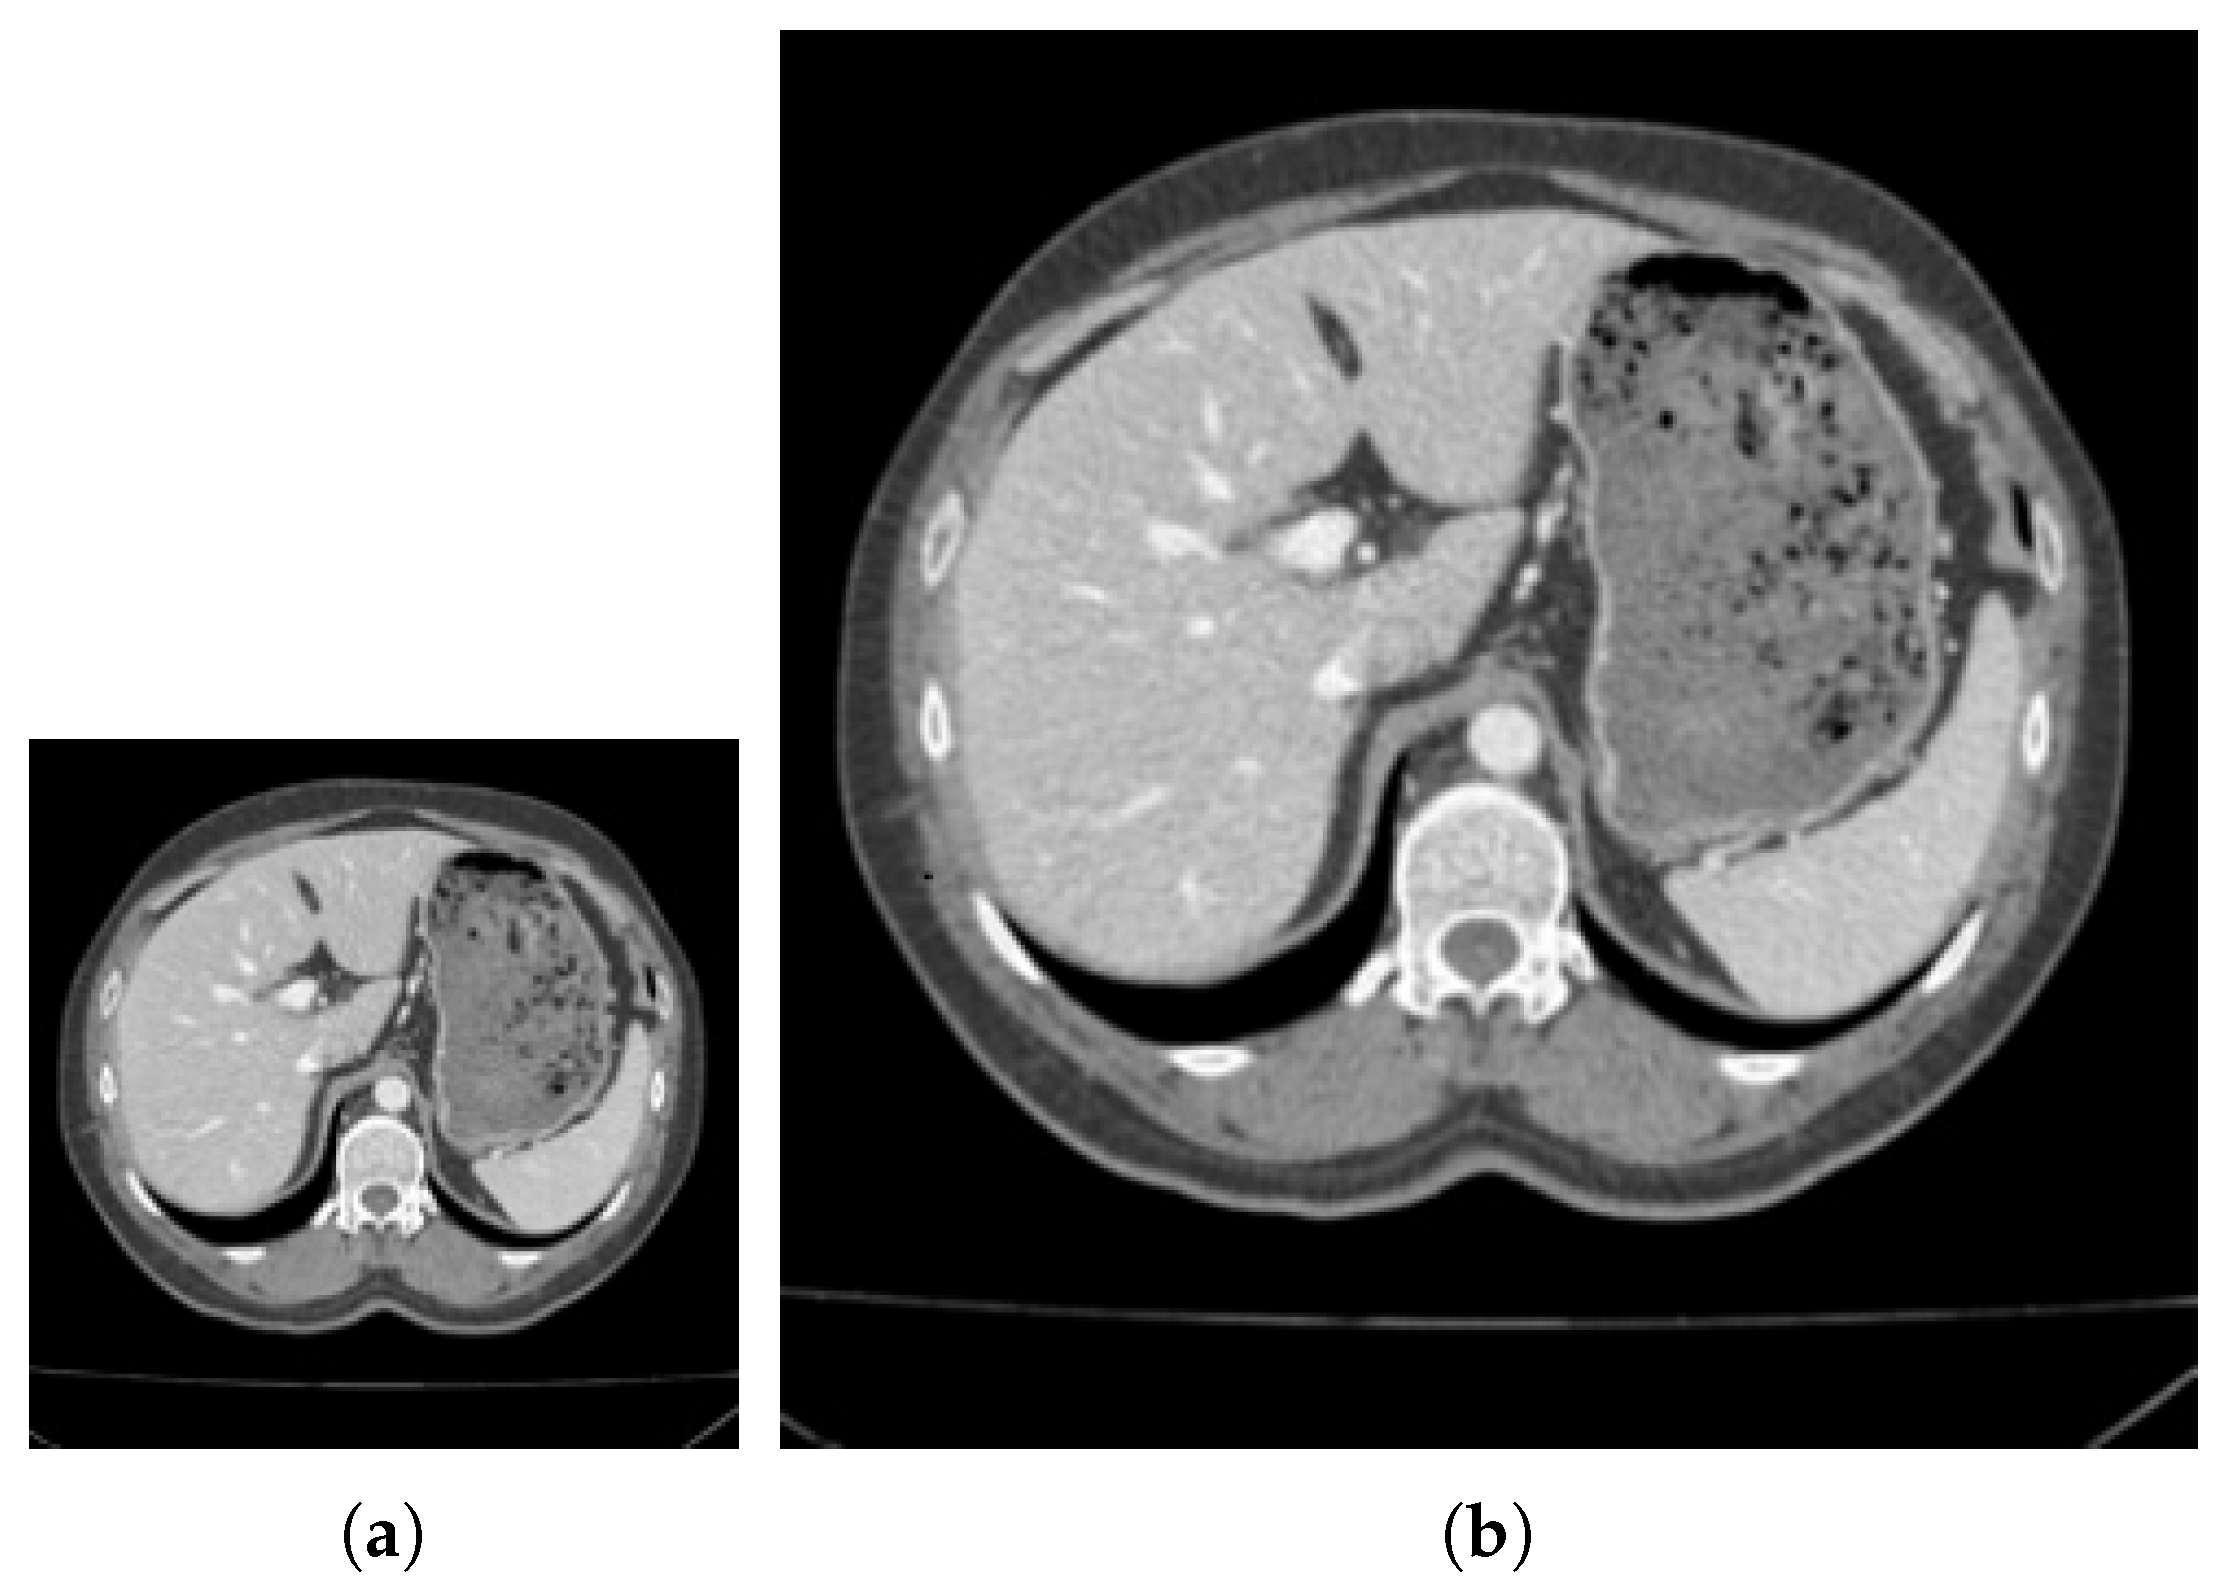

4.2. Verification of Medical CT Images with Proposed Method